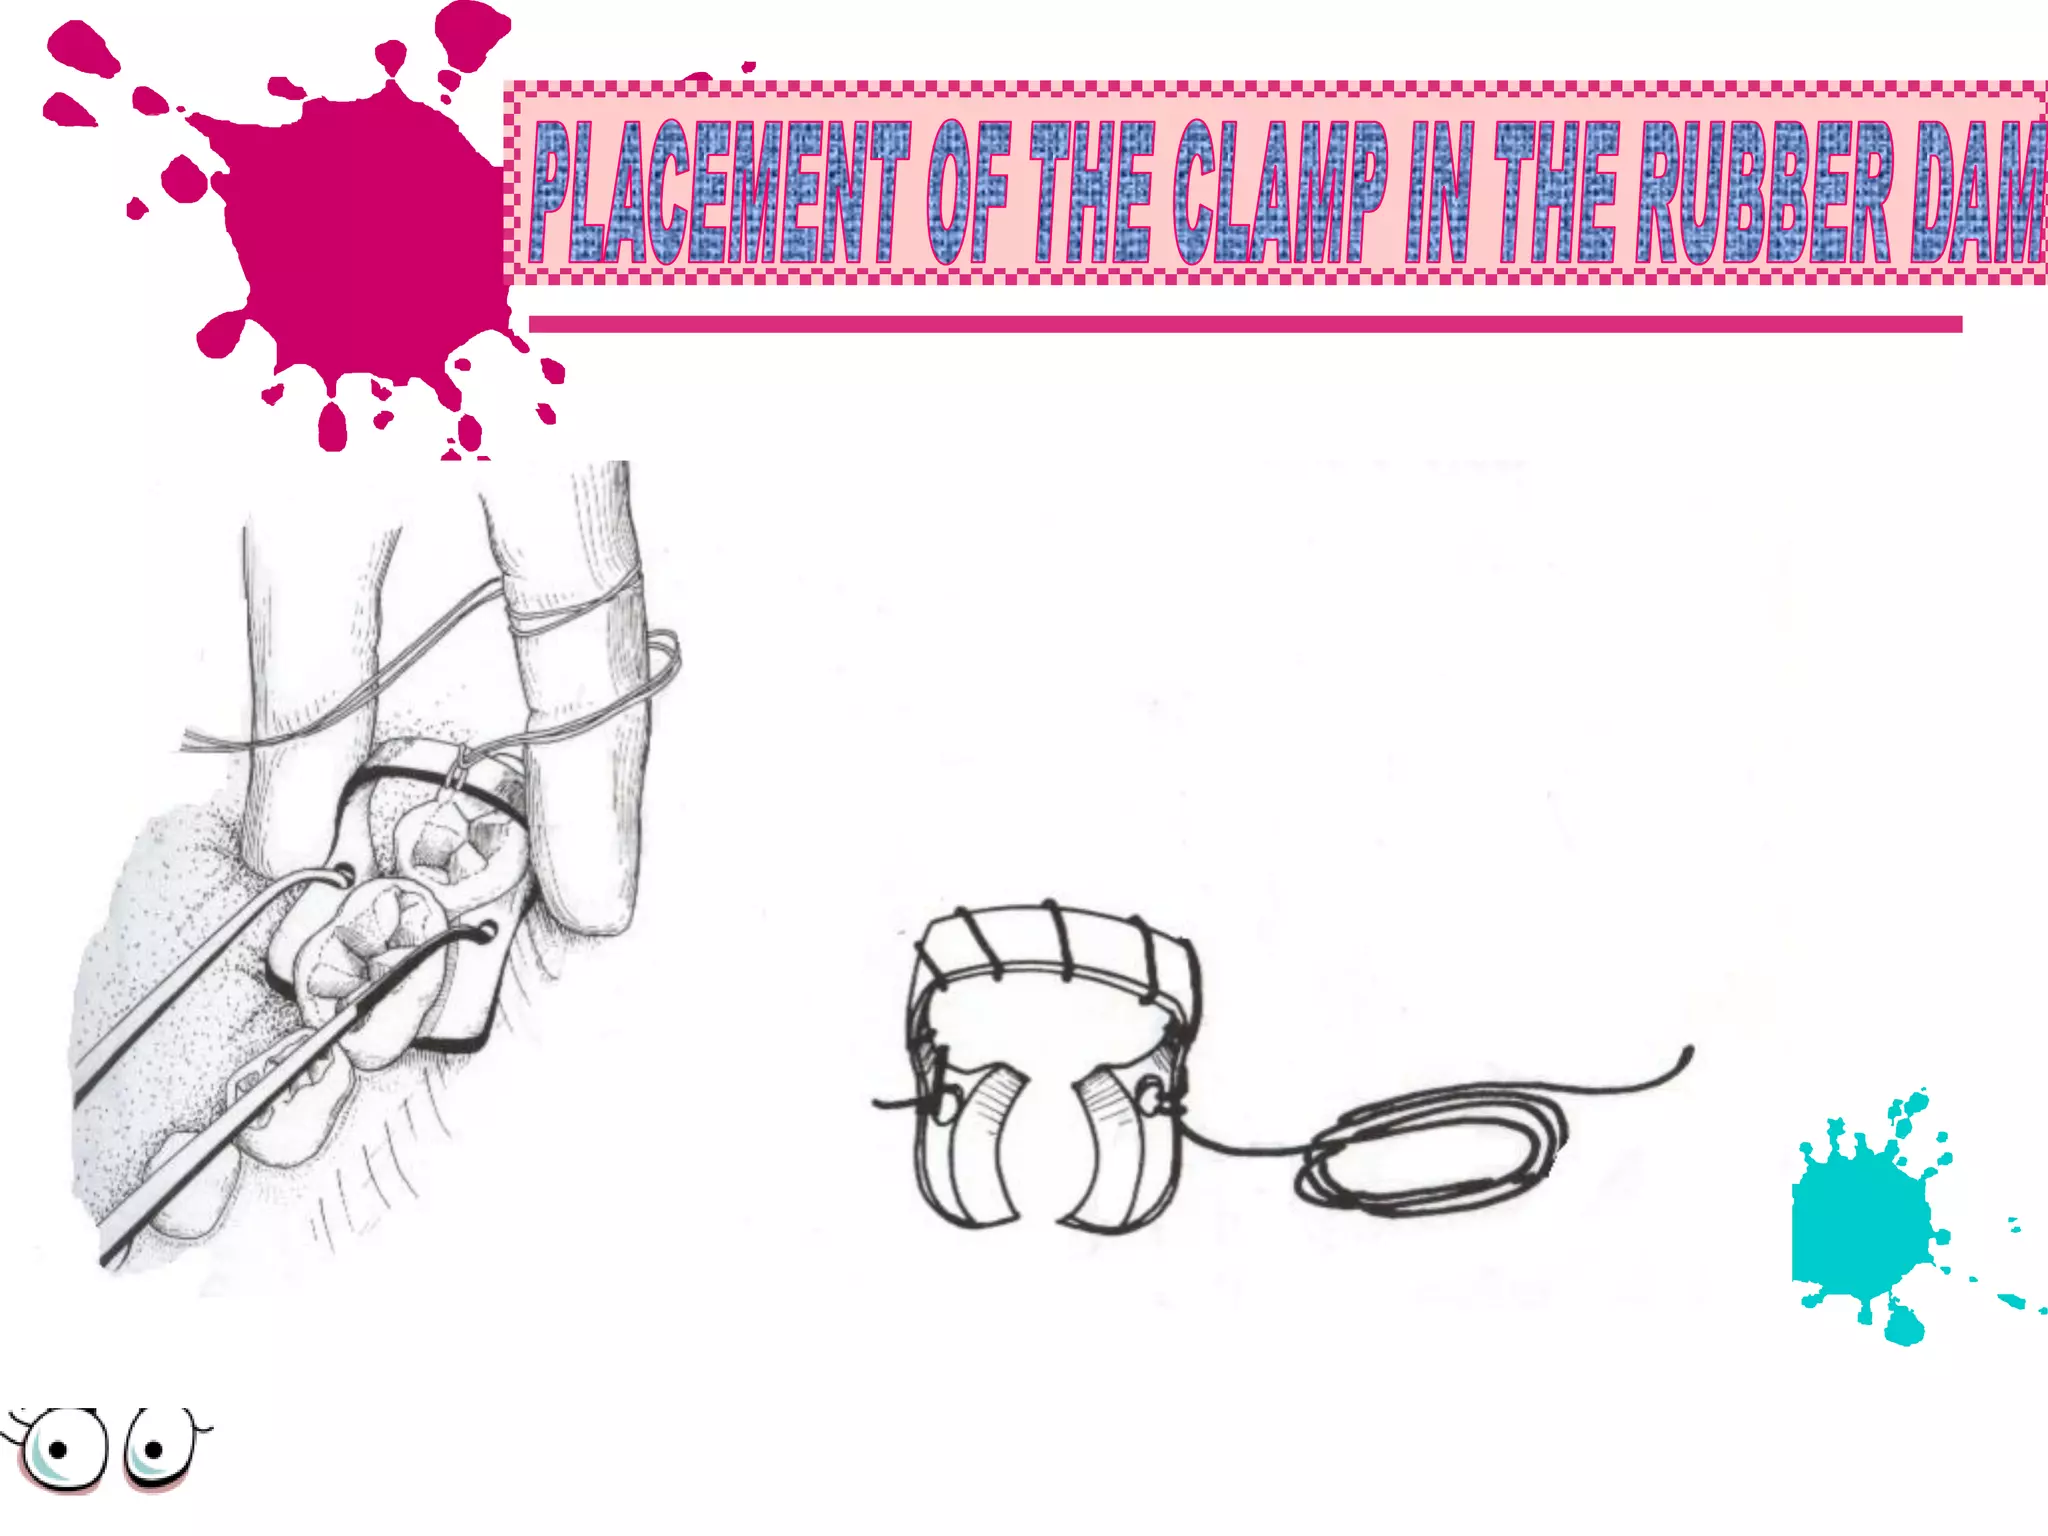

This document discusses the materials and components used for rubber dam isolation in dentistry. It describes the different types of rubber dam materials including color options and napkins to absorb moisture. It also outlines the tools needed such as punches to make holes, templates and stamps to guide hole placement, clamps to secure the dam, and other accessories like wedges and lubricant. Finally, it provides guidance on punching holes for different types of teeth and properly placing clamps in the rubber dam.